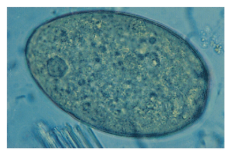

Ascaris lumbricoides (large intestinal roundworm) fert

knowt flashcard image